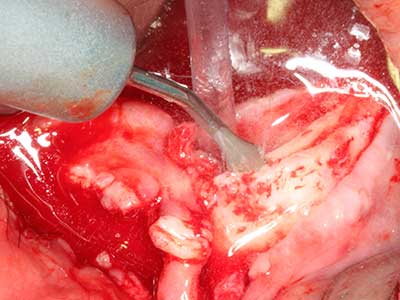

Aplicación: Obtención de hueso autógeno

Los injertos de hueso autógeno se utilizan en forma de bloques, escudillas, anillos y también se combinan con materiales de reemplazo óseo como virutas. Si el sitio del implante se prepara al mismo tiempo que el aumento, hay diversos sistemas de filtrado óseo que han demostrado su eficacia para la recopilación de las virutas óseas que se producen. Como alternativa, el sitio del implante se puede preparar usando un dispositivo de baja velocidad sin irrigación y si no se inserta ningún implante, es posible obtener virutas óseas de la periferia utilizando las rasquetas adecuadas. Esto también es posible aplicando cirugía piezoeléctrica con piezas especiales, y así se demostró en un estudio específico en el que se realizó una comparación directa con las virutas obtenidas con fresas redondas, ya que las virutas obtenidas con el método piezoeléctrico presentaron una mejor calidad (Chiriac, Herten et al. 2005).

En la extracción de bloques óseos la piezocirugía también presenta ventajas adicionales: Además de la alta precisión en la osteotomía que ya se ha descrito antes, se ha comprobado que el uso de los delgados insertos de sierra resulta especialmente cuidadosas con el hueso. Frente a esto, sobre todo cuando se usan las fresas de Lindemann, cabe esperar pérdidas en la extracción significativamente más altas debido al mayor grosor de la parte frontal del cabezal (Lakshmiganthan, Gokulanathan et al. 2012). La separación basal que se necesita en particular en los injertos de bloque extraídos de forma retromolar se ve facilitada mediante sierras perpendiculares especialmente previstas a tal fin, lo que permite considerar que la cirugía piezoeléctrica es un procedimiento preciso y seguro para la obtención de bloques de hueso en el área retromolar (Happe 2007) (fig. 1-12).